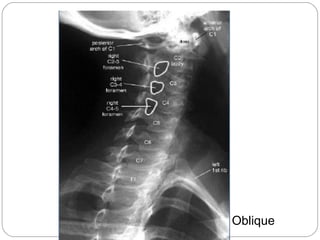

Views

Lateral

Oblique